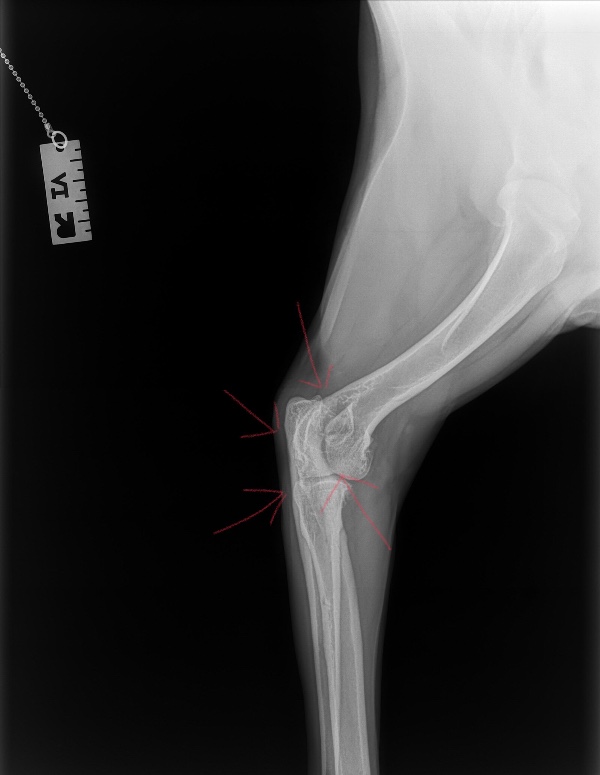

When Koda was five months old she was diagnosed with Genetic Elbow Dysplasia, and more recently Severe Advaced Osteoarthritis. Up until this point, we have managed her symptoms with diet, supplements, stretching, massage, swimming , and staying cautiously and consistently active with moderate hiking, walking and adventuring. In September she had an incident that acutely exacerbated her condition, and her pain got significantly worse. Some days, she tries to not use her effected leg at all, she can no longer hike, walk without extreme pain, run, jump, or play with any of her dog friends. She is only 1 and a half but is displaying the lameness and immobility you'd expect to see in an 11 year old dog.

When her pain got acutely worse in September we cut her exercise down to almost nothing, and transitioned her activity to swimming only, but her pain continued. We then started her on Adequan injections coupled with NSAIDs and a wider variety of supplements. When 5 weeks passed and we saw little to no improvement in her pain we were urged by our vet to seek the opinion of a Canine Orthopedic Specialist in Reno NV.

After meeting with him, and doing more diagnostic testing today he told us that because her Dysplasia and Osteoarthritis is so severe, at some point Koda will likely need to have her leg amputated in order to live a relatively pain free life. However, as a first step he strongly suggests an elbow surgery in hopes to buy her more time on four legs.

When Koda was five months old she was diagnosed with Genetic Elbow Dysplasia, and more recently Severe Advaced Osteoarthritis. Up until this point, we have managed her symptoms with diet, supplements, stretching, massage, swimming , and staying cautiously and consistently active with moderate hiking, walking and adventuring. In September she had an incident that acutely exacerbated her condition, and her pain got significantly worse. Some days, she tries to not use her effected leg at all, she can no longer hike, walk without extreme pain, run, jump, or play with any of her dog friends. She is only 1 and a half but is displaying the lameness and immobility you'd expect to see in an 11 year old dog.

When her pain got acutely worse in September we cut her exercise down to almost nothing, and transitioned her activity to swimming only, but her pain continued. We then started her on Adequan injections coupled with NSAIDs and a wider variety of supplements. When 5 weeks passed and we saw little to no improvement in her pain we were urged by our vet to seek the opinion of a Canine Orthopedic Specialist in Reno NV.

After meeting with him, and doing more diagnostic testing today he told us that because her Dysplasia and Osteoarthritis is so severe, at some point Koda will likely need to have her leg amputated in order to live a relatively pain free life. However, as a first step he strongly suggests an elbow surgery in hopes to buy her more time on four legs.